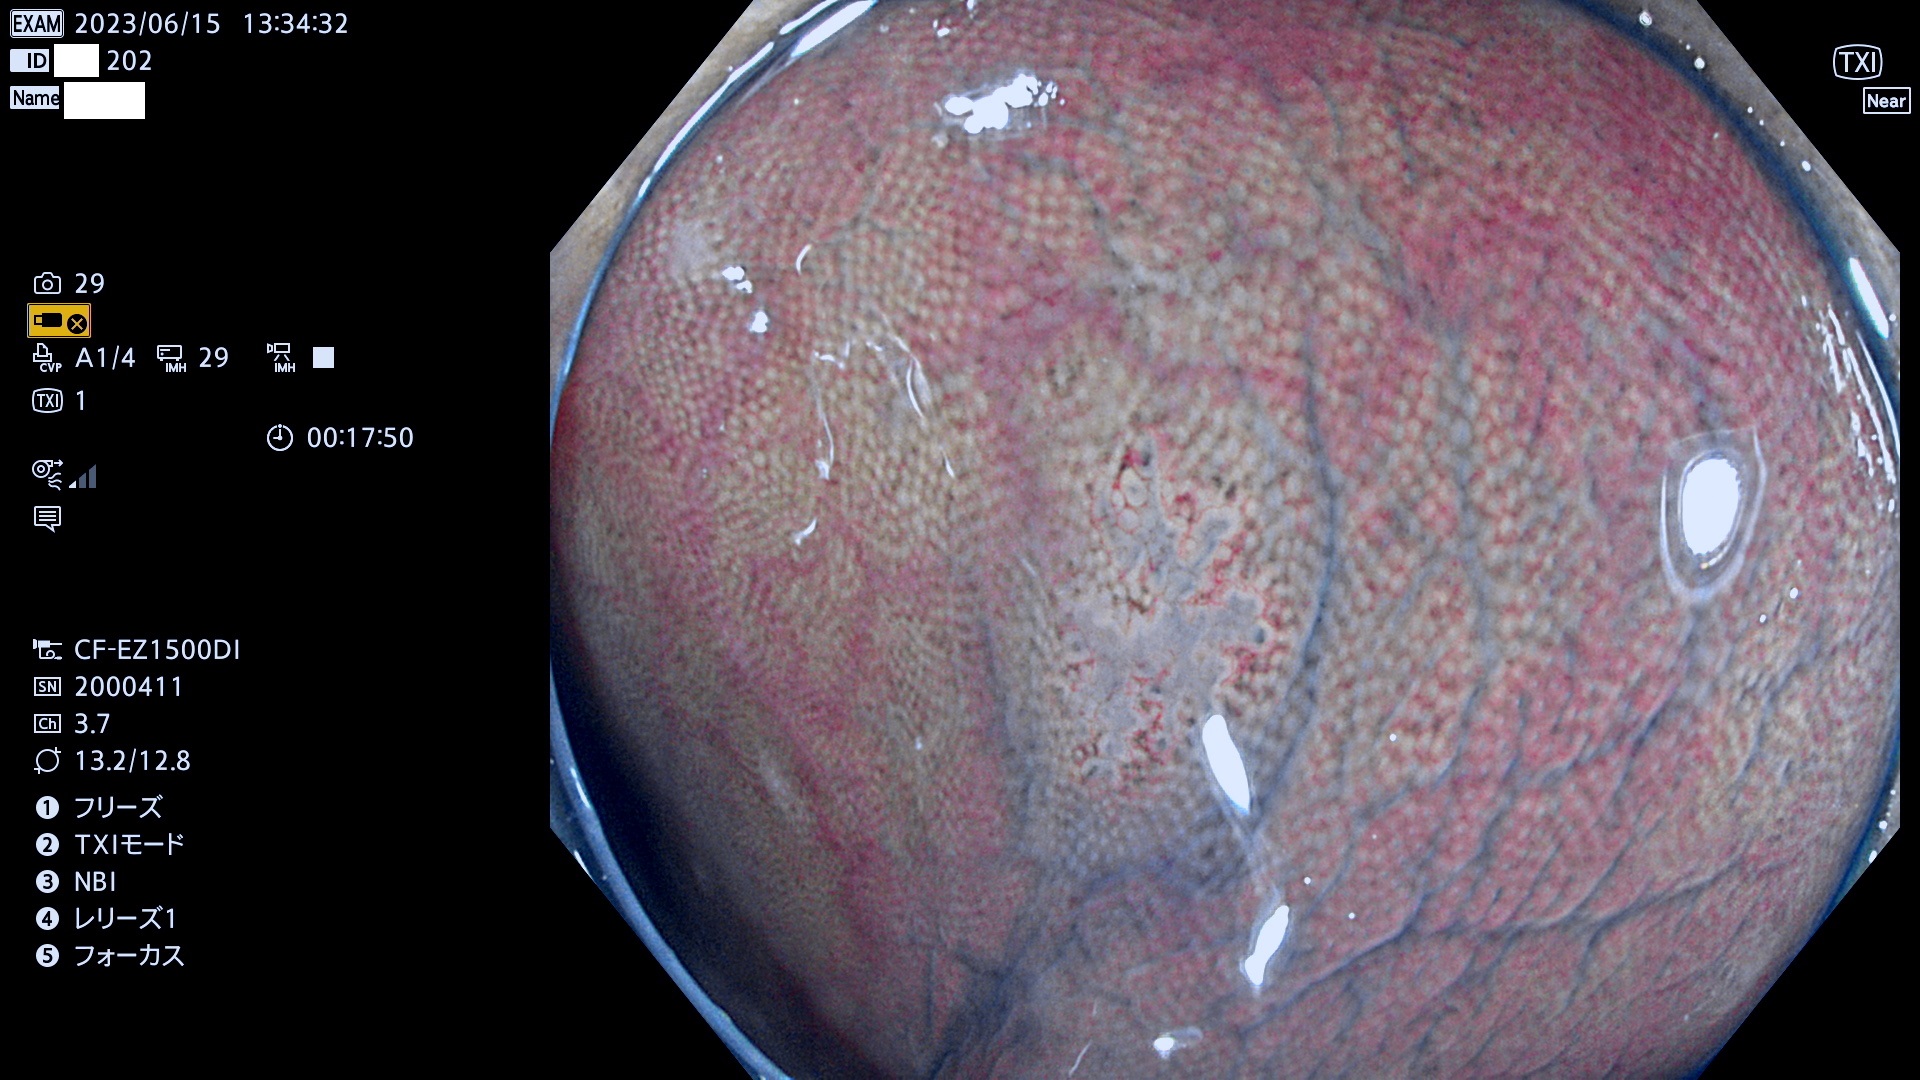

「表面型腫瘍」の中で、完全に平坦な物をUb、陥凹している物をUcと呼びます。平坦隆起型(Ua)よりも、発見が難しく危険な病変です。このタイプの発見率は「腺腫発見率」よりも、遥かに重要な意義があります。

抽出の対象期間 2023年6月15日(木)〜18(日)の4日間(48件の検査)4件